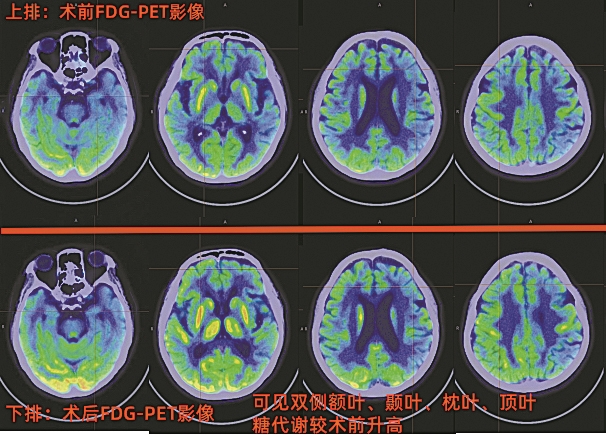

术后一个半月后,阿欣母亲在医院进行了术后PET—CT复查,FDG指标的检查结果发现,其颅内多个区域的糖代谢功能较术前有明显改善。“这说明手术是有效果的,患者脑部认知功能在慢慢恢复。”北京大学深圳医院核医学科主治医师杨红杰介绍说。